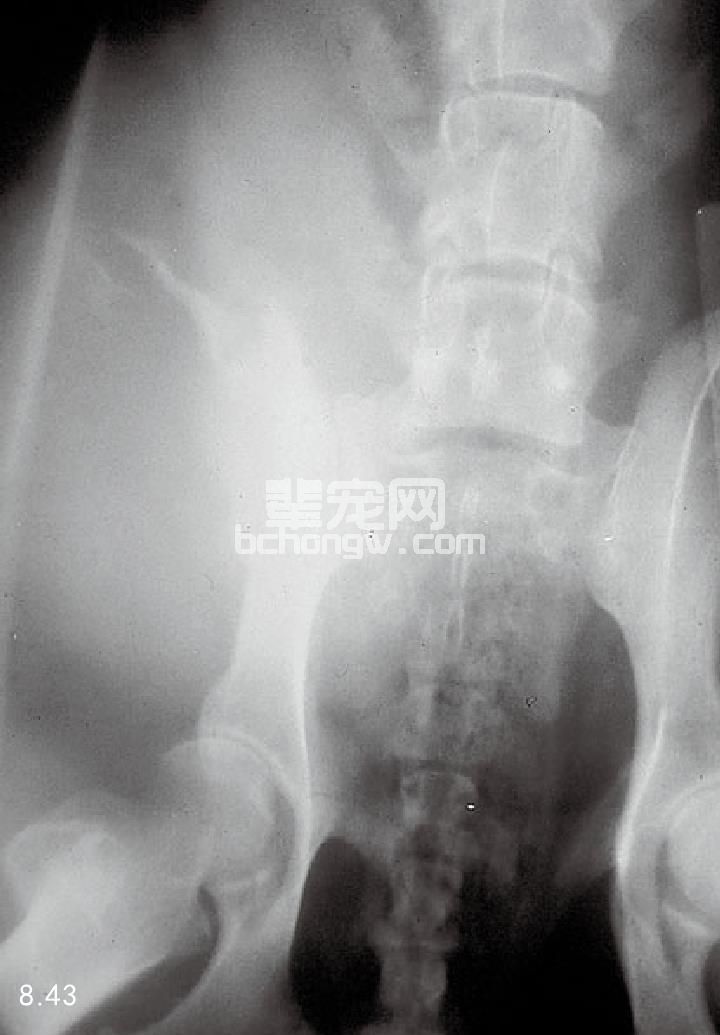

诊断 X线片显示,血管肉瘤破坏巨大,侵害一半或整个的骨干。破坏局限在骨髓腔内,向近端与远端扩 散。可以见到明显的骨膜下新骨形成,但无特征性(图8.43),也可能会发生病理性骨折。血管肉瘤常有血管 空间,活组织检查无诊断意义。因此,对肿瘤组织周围进行活组织检查要谨慎,要取得独特的肿瘤组织核心。

图8.43 骨盆血管肉瘤。这种疾病以软组织肿胀和腹膜增生为特点。